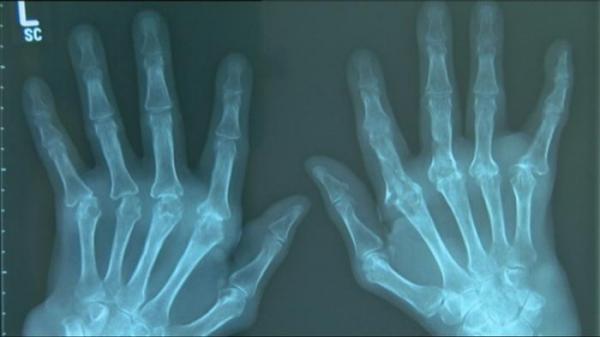

الفصال العظمي هو الروماتيزم

يطلق لفظ الروماتيزم عادة على التهاب المفاصل الذي يمكن أن يصيب أي من مفاصل الجسم. لكنه يظهر غالباً في مفاصل اليدين والأصابع، إذ يحدث التهاب يمكن أن يؤدي لتلف المفاصل لاحقاً أو الإصابة بآلام شديدة. أما الفصال العظمي فهو مرض يحدث بالعكس، بمعنى أن الأمر يبدأ بحدوث تلف في الأنسجة المفصلية يؤدي إلى حدوث التهابات مؤلمة، ذلك أنه يصيب الأنسجة التي تعمل على تقليل الاحتكاك بين المفاصل نتيجة الحركة.